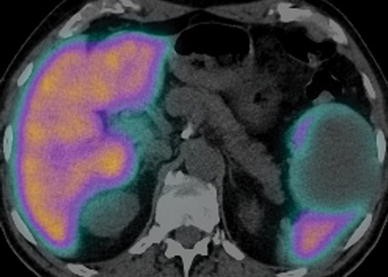

Fig. 1

figure 1

SANT of the spleen: 2-[18F]-Fluoro-2-Deoxy-D-Glucose (FDG-PET) findings. Axial fused image shows intense tracer activity (standard uptake value = 4.5) within the splenic lesion.

Only one prior published report of the FDG-PET behavior of splenic SANT is known [13]. These authors [13] indicated that splenic SANT shows hypermetabolic activity on FDG-PET, simulating neoplasm; our lesion showed similar behavior. The abundance of cells, including hemosiderin-laden macrophages, myofibroblasts, lymphocytes, and plasma cells, may account for splenic SANT’s FDG avidity.